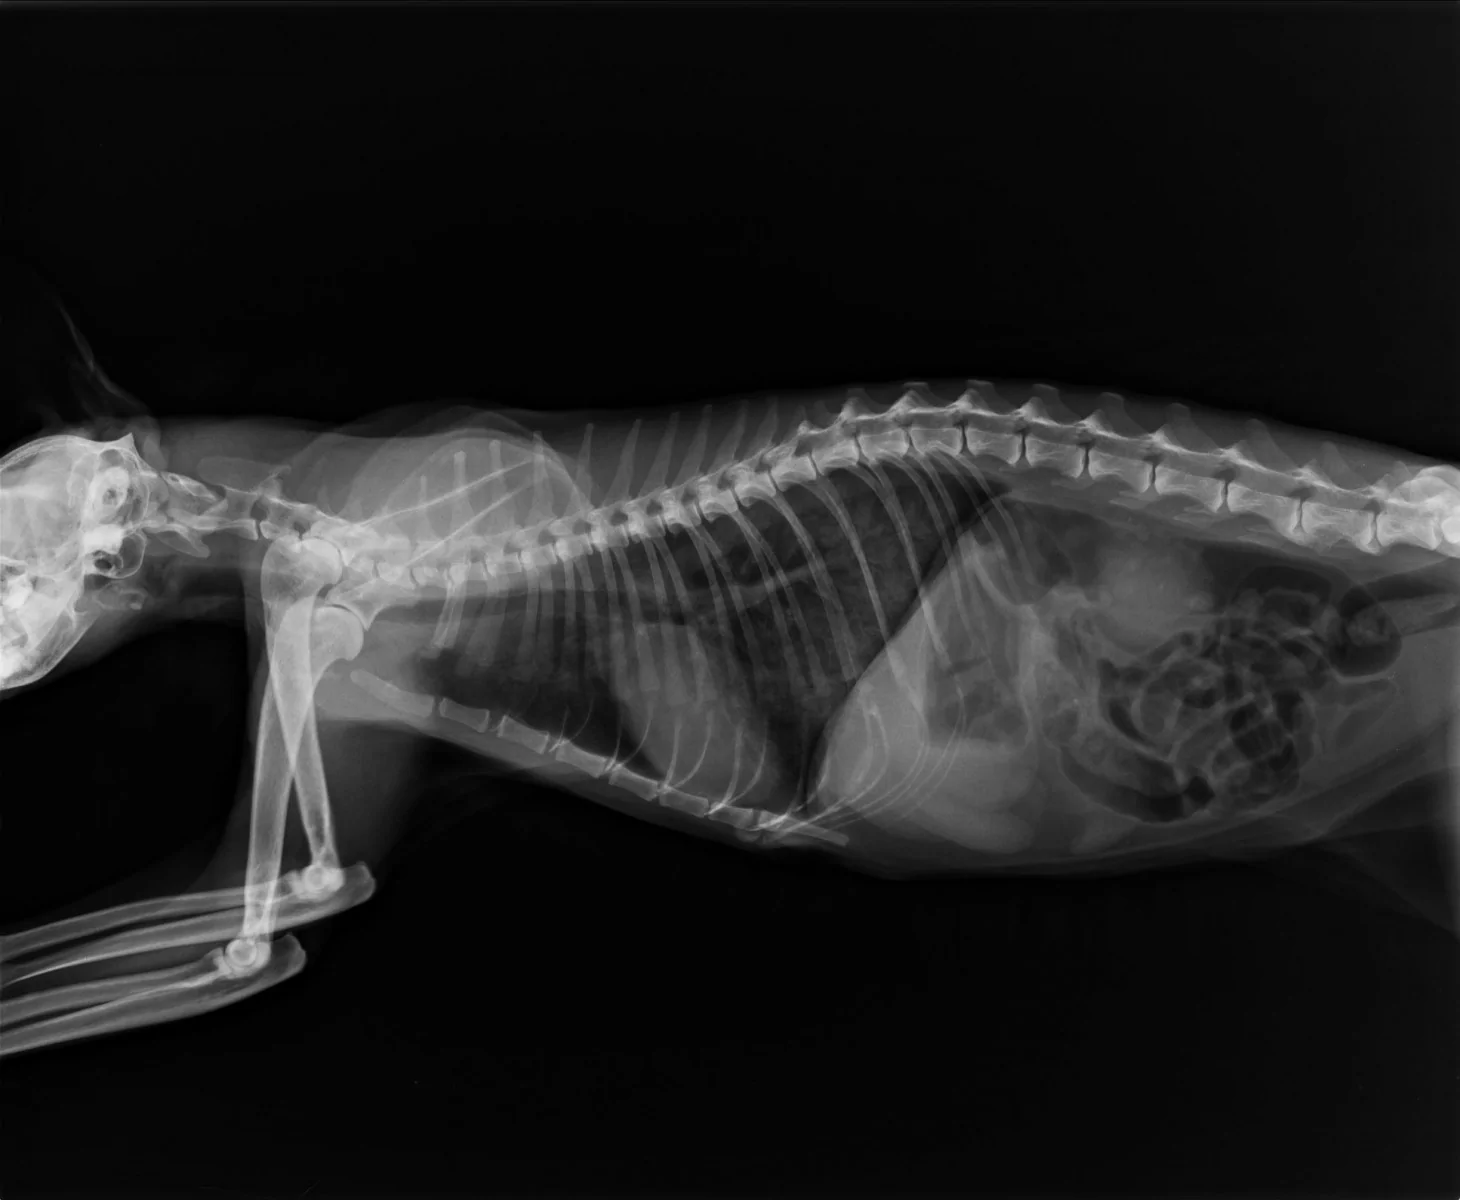

Рентгеновские снимки головы кошки в боковой проекции